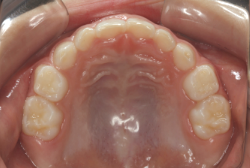

凸凹を主体としたケースの場合、当院の平均治療期間は18ヶ月ですので、このケースは少し長めに経過しました。理由の一つは凸凹の程度がかなり重症だったと言うことですが、もう一つは、右下第2大臼歯が45度くらい前傾していたため、それを整直化させるために時間を要したと考えています。いずれにしても最終結果は大変よい状態と思います。